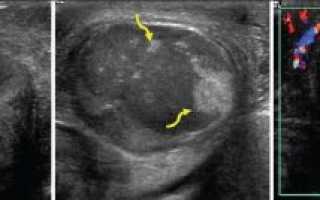

Фото. А — Мужчина 24-х лет после тупой травмы левого яичка. На УЗИ яичко неоднородной эхоструктуры, с неровным контуром, нарушенной белочной оболочкой, пролабирование паренхимы (звездочка); анэхогенный ободок, вероятно, гематоцеле вследствие разрыва яичка. Б, В — На УЗИ контур яичка неровный, белочная оболочка нарушена, пролабирование паренхимы (стрелки), гематоцеле, в части яичка кровоток не определяется. Диагноз: разрыв яичка, гематоцеле, сегментарный инфаркт.

Фото. Мужчина 26-ти лет после тупой травмы мошонки. На УЗИ контур яичка неровный, белочная оболочка нарушена, паренхима пролабирует (толстая стрелка), вероятно, разрыв яичка; яичко гипоэхогенное, кровоток не определяется (стрелки), что указывает на инфаркт; небольшие гиперэхогенные зоны (волнистые стрелки) — это сохранная паренхима.